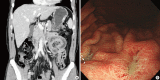

Plexiform angiomyxoid myofibroblastic tumor (PAMT) of the stomach is a recently recognized entity. Because of its rarity, only 22 cases have been reported in the English-language literature and most of these are single case reports. We report two cases of gastric PAMT. The tumor cells were bland and plexiform arranged in a myxoid stroma, which was positive for alcian blue. Immunohistochemically, the tumor cells were positive for smooth muscle actin, but negative for c-kit, CD34, desmin, S-100 protein, epithelial membrane antigen, neurofilament, and protein kinase C-theta. Mutation analyses for exon 9, 11, 13, and 17 of KIT genes and 12, 14, and 18 of the platelet-derived growth factor receptor alpha (PDGFRA) genes were performed and the tumors were wild-type for mutation.